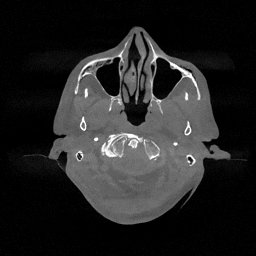

III-D Real Clinical Data Experiment

The experimental results on clinical head data are shown in Fig. 4. The reference images were reconstructed using the fast iterative shrinkage-thresholding algorithm (FISTA) with total variation regularization from non-truncated projection data. In the WCE reconstructions (Fig. 4(b)), severe truncation prevents accurate recovery of anatomical structures outside the FOV. Despite being trained solely on simulated data with a domain gap, all deep learning models can restore a substantial portion of the missing anatomy. Among them, the diffusion-based methods recover soft-tissue boundaries more faithfully than the conventional deep learning approach FBPConvNet, highlighting their stronger image generation capability. However, cDDPM reconstructions exhibit more noticeable noise than those from other methods, consistent with the simulated data results. The patchDiffusion model introduces artifacts within the FOV, likely due to its patch-wise processing strategy. While I2SB shares the same limitations as other diffusion models in perfectly restoring soft-tissue detail, it produces fewer residual noise patterns and fewer artifacts within the FOV boundaries. Overall, Fig. 4 demonstrates the strong efficacy of I2SB in reconstructing real CBCT data.